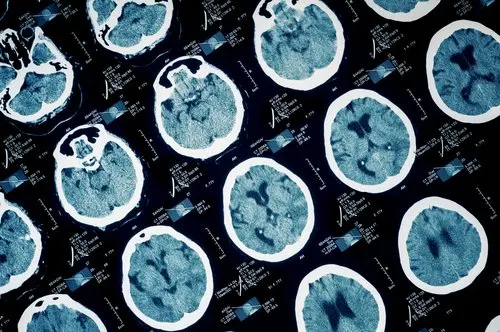

- Síntomas neurológicos.

- Esclerosis Múltiple.